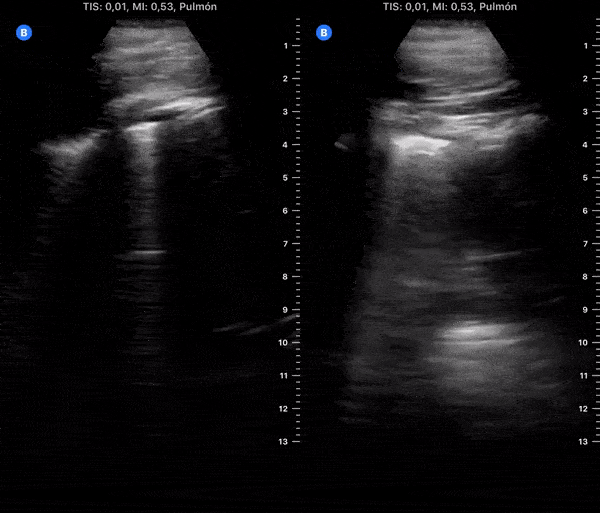

COVID 19 Lung US Disease Progression - Day 6

Day 6 after #COVID diagnosis. Less cough, bit tired, still no dyspnea. No fever. Oxygen saturation 98%. #POCUS update: thick pleural line, b-lines and subpleural consolidations tend to resolve. Significant lung improve from yesterday. @yaletung